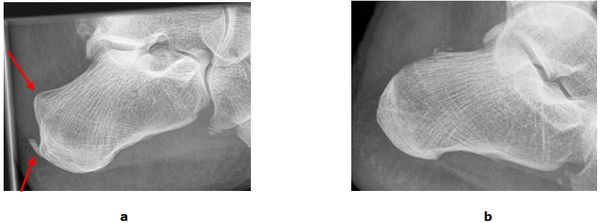

Abb.2: a Großer Kalkherd in der Sehne. b Röntgenbild nach der operativen Entfernung unter Erhalt der Sehne.

Abb.3: a Sehnensporn und Haglund Exostose im präoperativen Röntgenbild. b Das Fersenbein ist modelliert und die störenden Knochenüberstände wurden entfernt. Der Patient kann wieder schmerzfrei laufen.